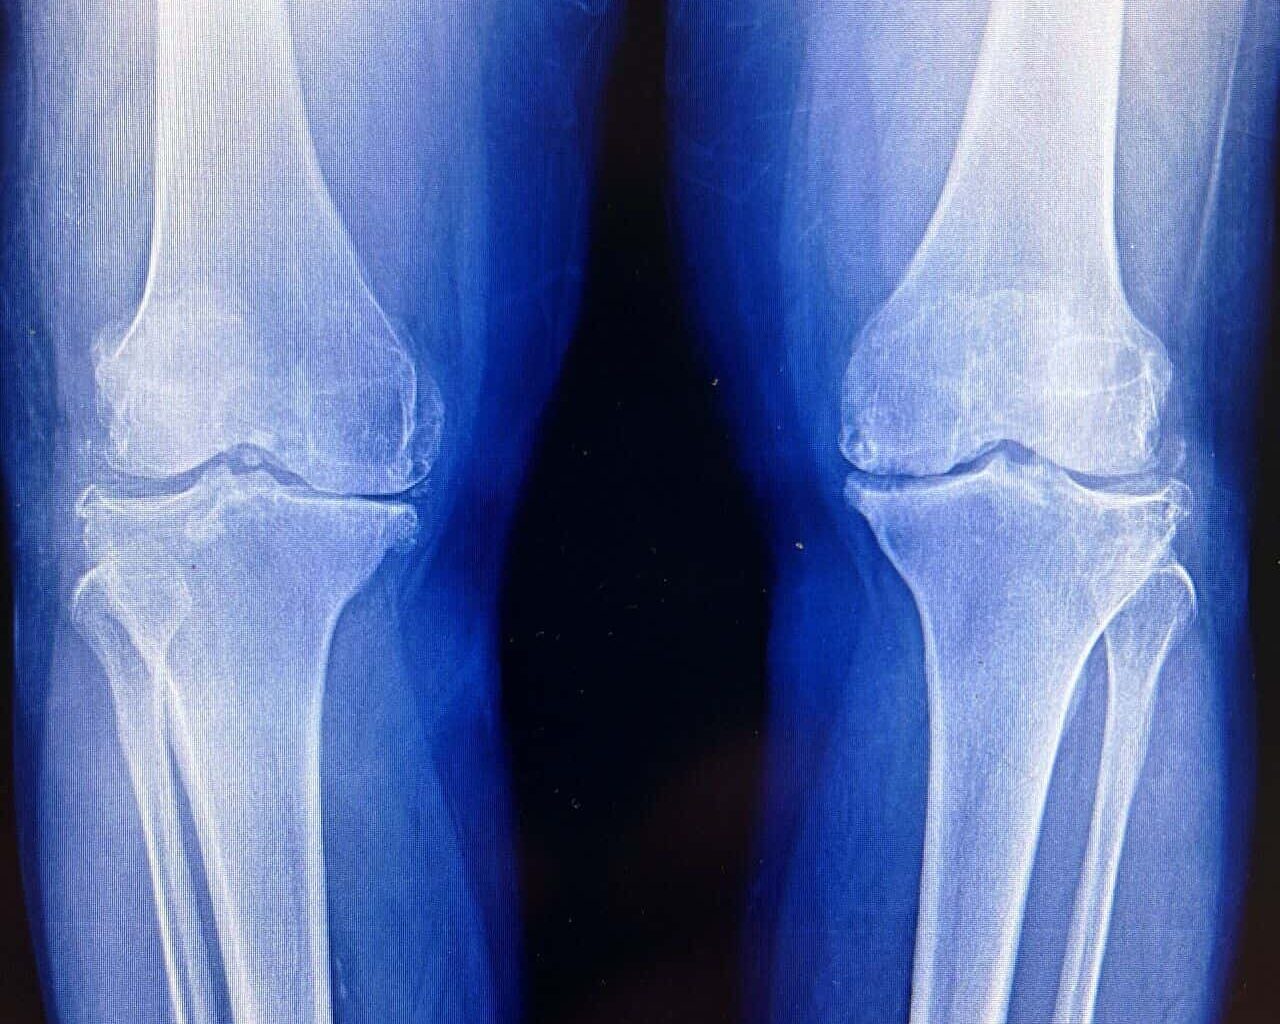

Cartilage is the body’s most stubborn tissue. Once it wears away, it’s usually gone for good. This biological dead-end is the engine behind osteoarthritis, a grueling condition that stiffens joints, fuels chronic pain, and eventually forces millions of people into the operating room for total joint replacements.

The findings arrive amid a broader push to develop treatments that modify osteoarthritis itself, rather than simply easing pain. About one in five adults in the United States has the disease, which estimates costs of tens of billions of dollars a year in direct health care expenses. Current drugs do little to slow cartilage loss. When joints fail, surgery is often the only option.